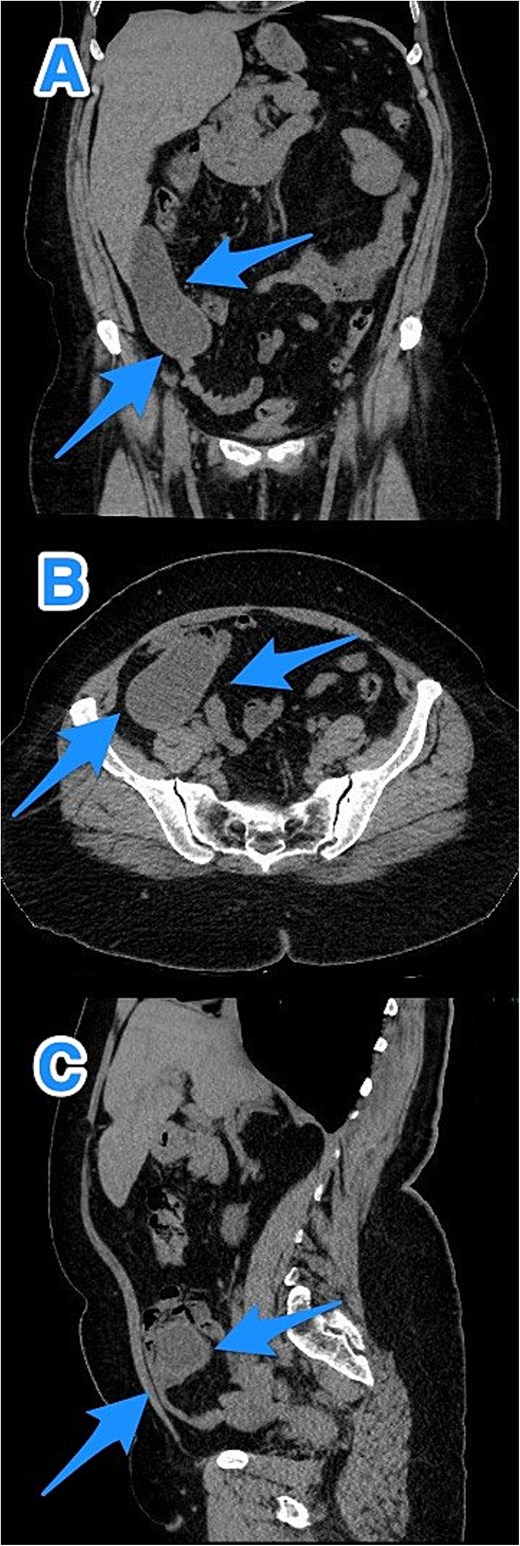

CT abdomen and pelvis with contrast: (A) coronal, (B) axial, and (C) sagittal views demonstrate a dilated, blind-ended structure in the right lower quadrant with incomplete circumferential calcifications and thick fluid content, consistent with an appendiceal mucocele (arrows).

CT abdomen and pelvis with contrast: (A) coronal, (B) axial, and (C) sagittal views reveal an appendix measuring 22 cm in the right iliac fossa, with edematous wall thickening, minimal surrounding fat stranding, and an adjacent fluid collection measuring 3.3 × 1.8 × 8.5 cm, consistent with a perforated appendix (arrows).